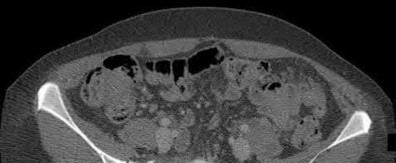

2. # A 35-year-old woman is involved in a head-on collision while driving. Initial radiographs are shown in Figures 8a and 8b. Injury to what vessel increases the risk for osteonecrosis of the injured bone?

5. Artery of the tarsal sinus Corrent answer: 4

The patient has a Hawkins type III talar neck fracture-dislocation with a risk of osteonecrosis ranging from 69% to 100%. Anatomic studies have shown that the artery of the tarsal canal supplies the lateral two thirds of the talar body.

The other vessels listed provide no significant contribution to the talus.